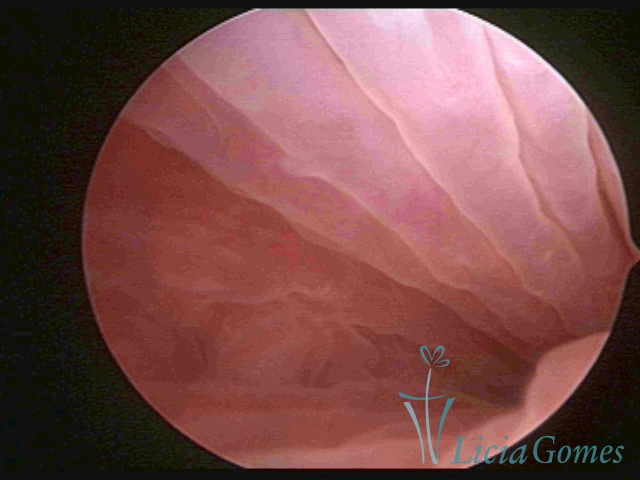

Second part or middle section

In the middle section of the cervical canal, the details of the buds are lost. It is possible to view creases and crypts. Longitudinal grooves are frequently observed. They are the most compact tissues presenting the most vascularized surface, whose vessels follow its passageway.